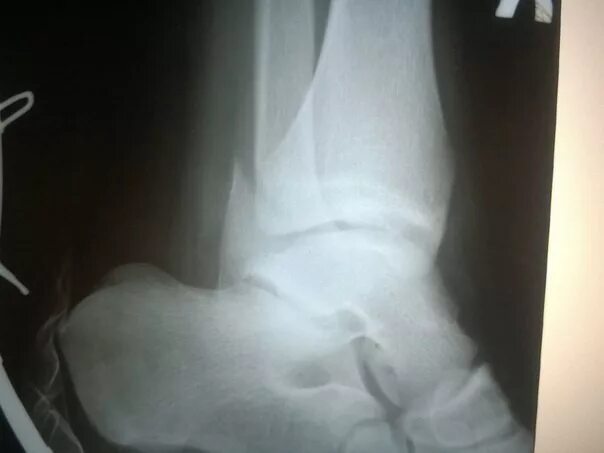

Через сколько срастается перелом лодыжки